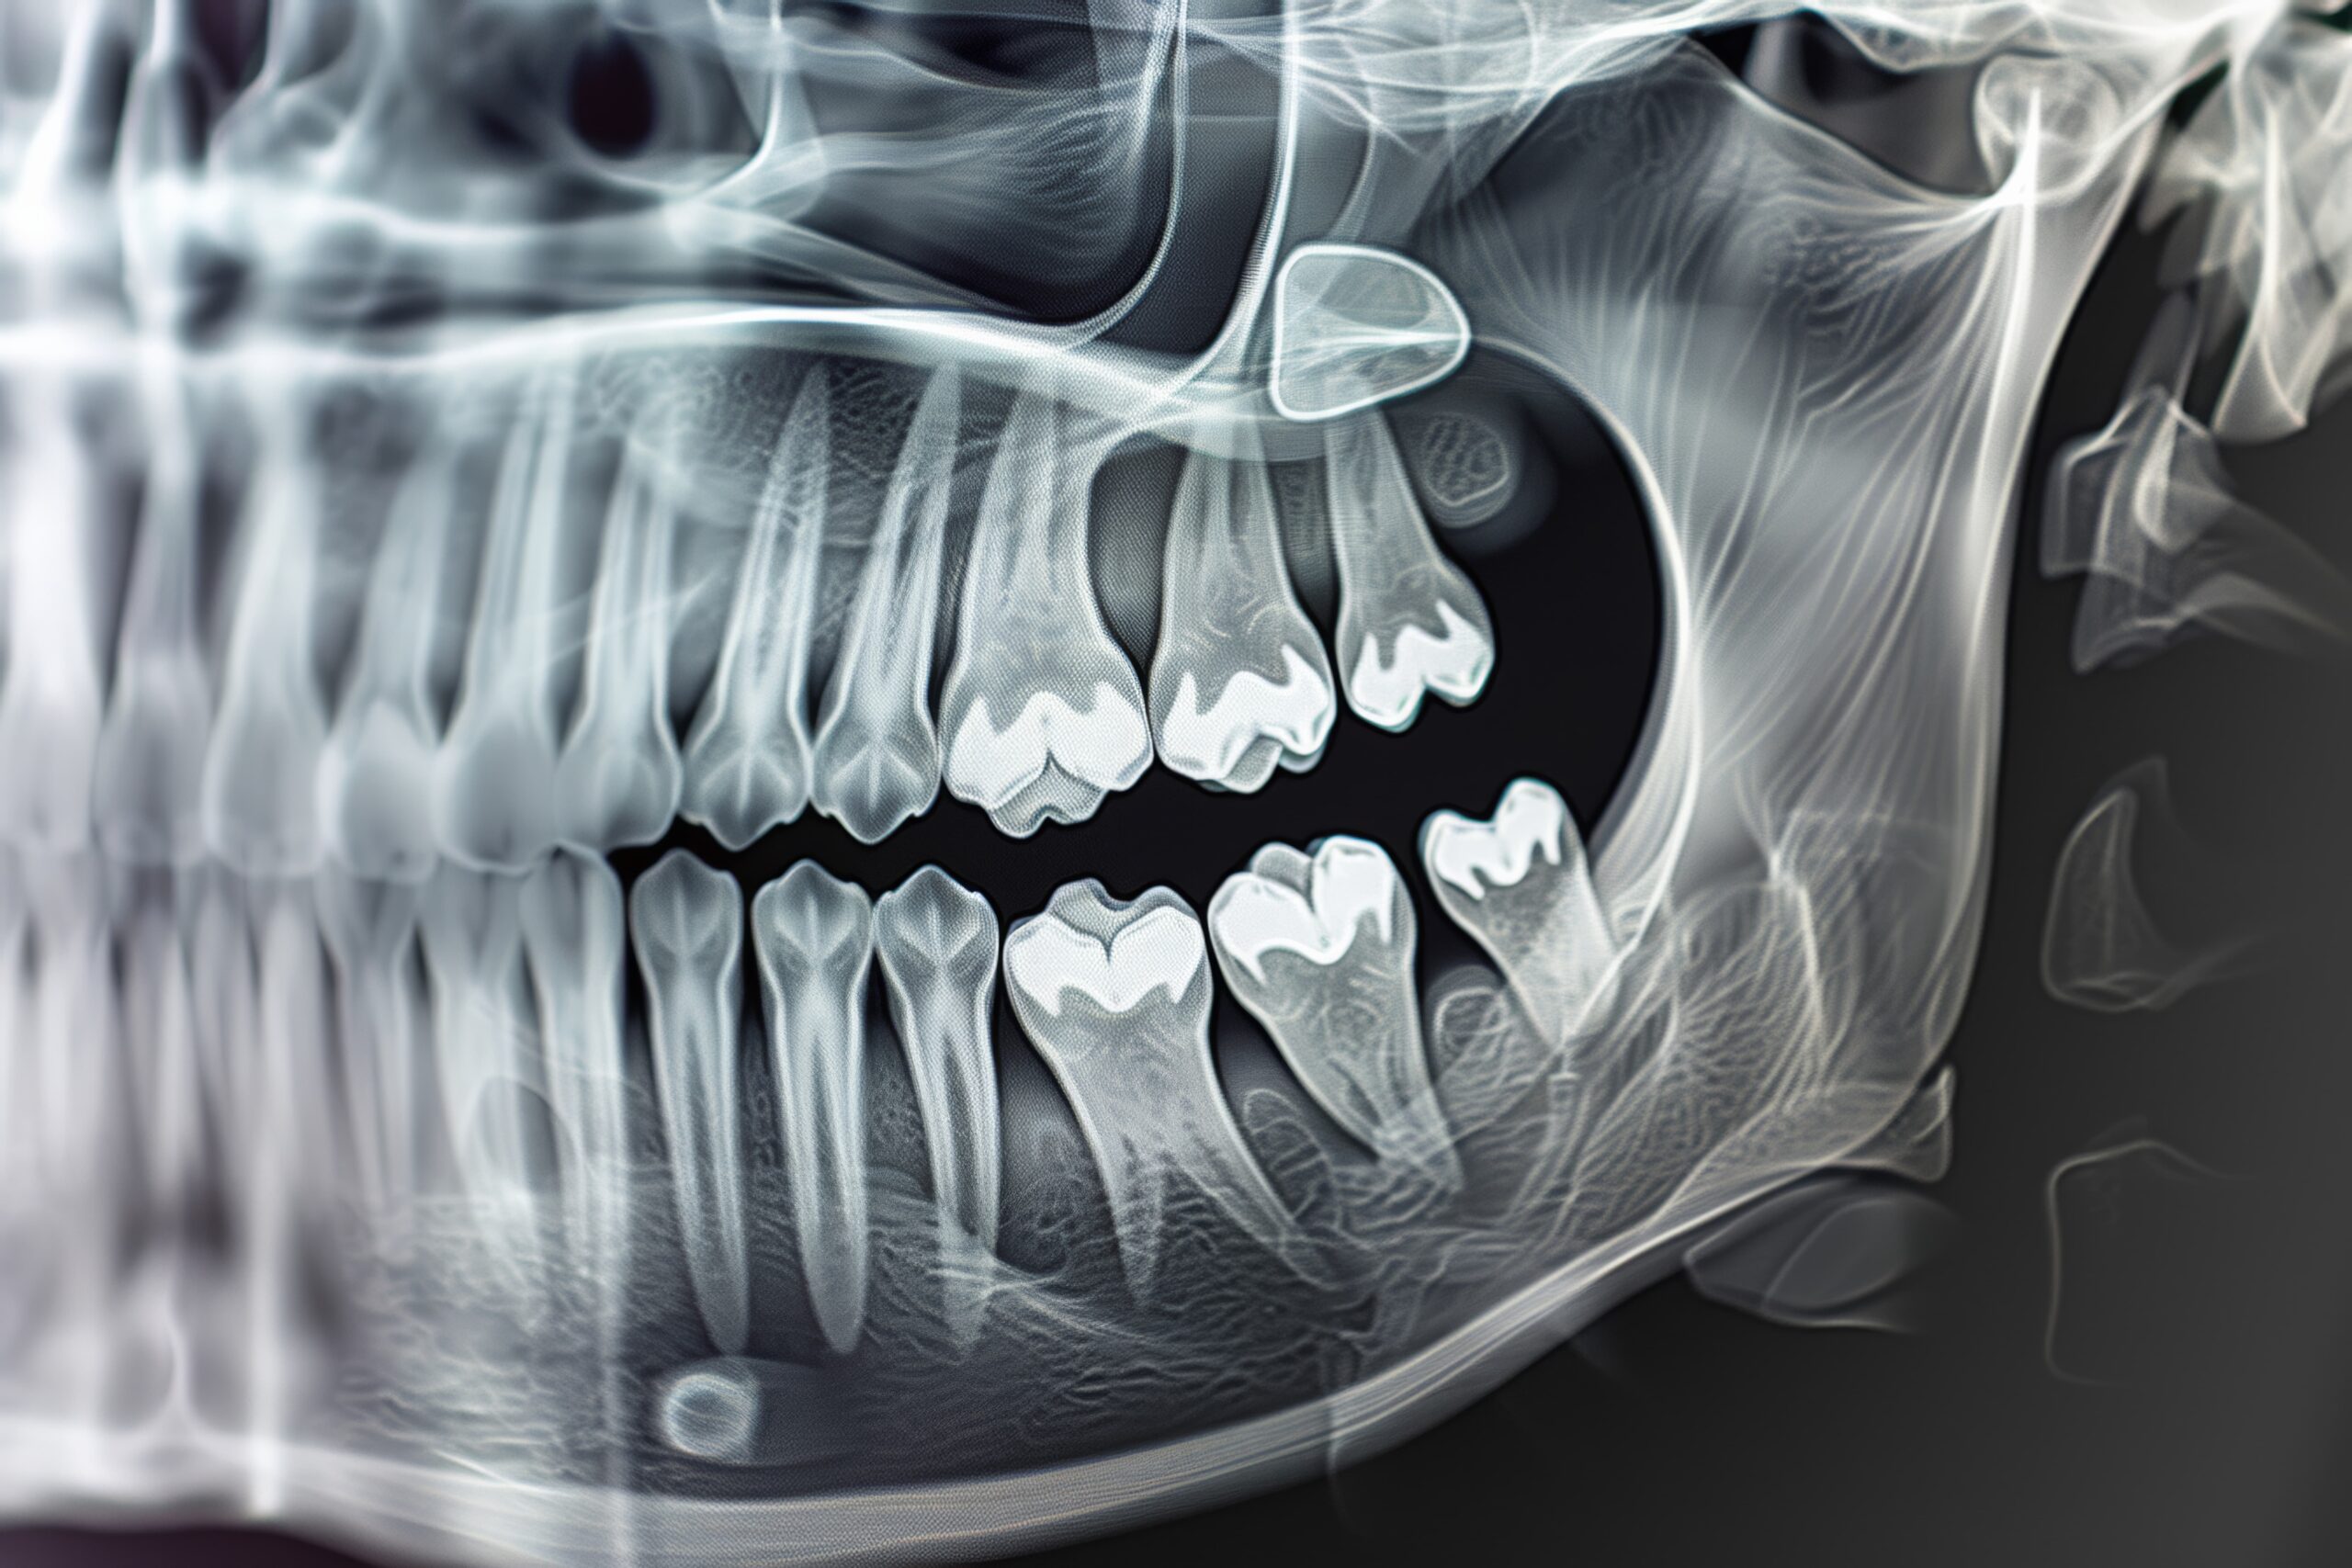

親知らずの抜歯を行う前に、まず歯科医師によって診察が行われます。レントゲン撮影をして、親知らずの位置や状態、周囲の歯や神経との関係を確認します。これにより、抜歯の難易度や必要な処置が判断されます。